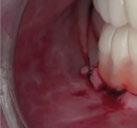

Dado que la estabilidad primaria se ha conseguido en la mayoría de los implantes, coincidiendo con la previsión propuesta en la planificación, procedemos ahora a la fase protésica. En el caso que nos ocupa, la paciente reside lejos, por lo tanto, colocamos tapones sobre los pilares transepiteliales y descansa en la sala de recuperación (Figura 30).

El procedimiento de diseño, impresión, pulido y cementación de aditamentos consume

Figura 34. Rehabilitación superior impresa en resina Bego VarseoSmile TriniQ® lista para atornillar. Se han anulado de la oclusión aquellos implantes que no obtuvieron una estabilidad primaria superior a 35 N/cm2 Figura 31. Escaneado intraoral postcirugía. Figura 32. Rehabilitación recién impresa a través de impresora Varseo XS con resina Bego VarseoSmile TriniQ®. Figura 33. Ajuste pasivo entre aditamentos protésicos y la rehabilitación impresa.

aproximadamente una hora y media. Usamos resina Bego VarseoSmile TriniQ® para puentes definitivos. Aunque en este caso la vamos a usar para confeccionar unas prótesis fijas atornilladas provisionales de larga duración, dado al aumento de dimensión vertical que vamos a realizar a la paciente, de esta forma obtendremos una neuroprogramación de la ATM reinstaurando una Dimensión Vertical apropiada y mejorando la estética facial de la paciente. Excluimos de la carga aquellos implantes que no obtuvieron una estabilidad primaria superior a 35 N/ cm2. El material permite la realización de una carga inmediata en material definitivo en puentes (Figuras 31 a 38).